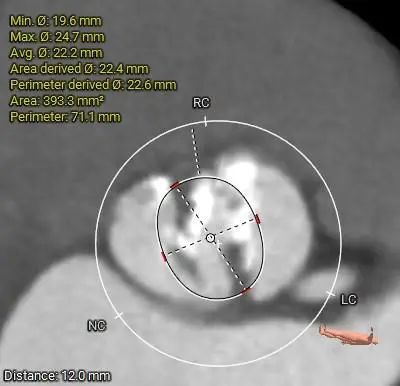

ANNULUS

12mm SUPRA ANNULUS